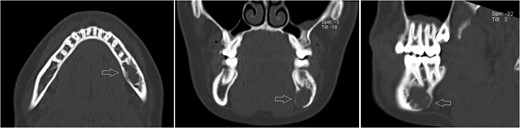

Follow-up panoramic X-ray imaging at 12 months after initial diagnosis showing no significant progression of the tumor lesion.

Likewise to panoramic X-ray, follow-up CT after 12 months showing no significant progression of the lesion.